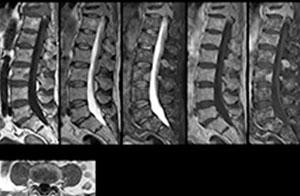

“We use mDIXON TSE extensively in our spine imaging in the emergency room,” says Dr. Karis. “It’s particularly nice in that it is very robust with regard to susceptibility type of problems that would come up with traditional spectral fat-saturated images; these problems are essentially eliminated with the mDIXON technique. In our ED environment it’s really nice to have the fat-free imaging that goes along with the mDIXON technique.

“For the thoracic and cervical spine routine non-contrast exam, for example, we perform one mDIXON T2 TSE sequence, which provides us with two outputs: the fat-and-water-together T2-weighted images, as well as the water-only sagittal T2-weighted images. And then we also perform an axial gradient echo exam.”

Cervical spine routine exam

This patient presented with headache that was worse with neck flexion and we see a Chiari 1 malformation with low-lying cerebellar tonsils as well as some degenerative cervical thrombolytic change.